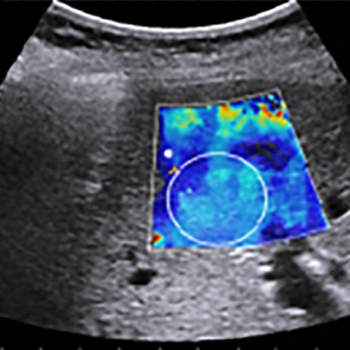

That’s why a special method was developed called Shear Wave Elastography (SWE). In this method, a certain kind of tiny vibration or shear wave is sent inside the body. These waves spread sideways, and by measuring their speed (shear wave speed), we can determine how hard or soft the tissue is. The faster the wave travels, the harder the tissue—that’s the main concept.

So SWE is a non-invasive (meaning without surgery), real-time (meaning immediate) and affordable technology that is now routinely used by doctors in many advanced countries.

This produces a perfectly clear stiffness map, which helps doctors easily distinguish between hard and soft areas inside the body.